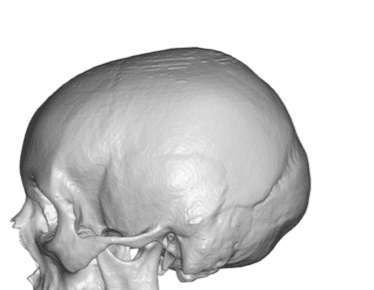

Desire for an improved head shape so that it looks rounder and not so peaked or sloped.

Placement of custom skull implant for parasagittal augmentation to create a rounder head shape. An example of what appears to be a high sagittal crest that is really low parasagittal skull areas.

Desire for an improved head shape so that it looks rounder and not so peaked or sloped.

Placement of custom skull implant for parasagittal augmentation to create a rounder head shape. An example of what appears to be a high sagittal crest that is really low parasagittal skull areas.